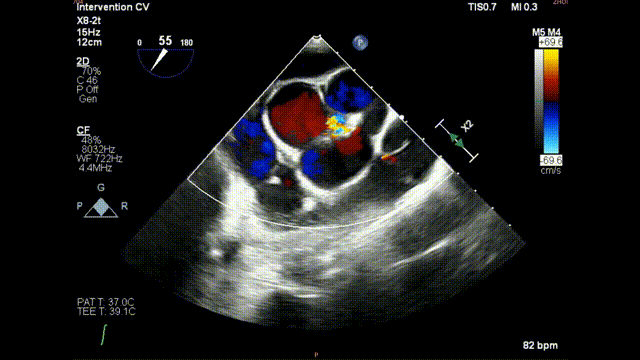

术前食道超声示:

术前食道超声-短轴 color

术前食道超声-长轴 color